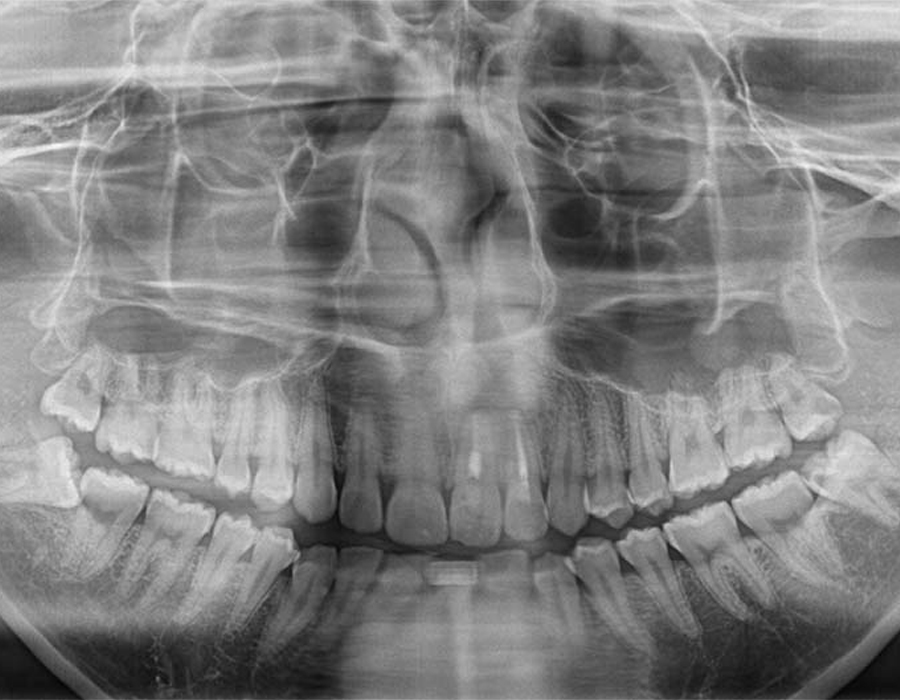

STEP 02検査&検診

短時間で安全に親知らずを抜歯するためには、事前の画像検査が欠かせません。CT撮影により、親知らずや顎の骨の状態を詳しく知ることができます。その上でお口の中を拝見します。現状と歯科医としての意見をお伝えし、患者様と話し合いながら、抜歯を行うのか、残して経過観察に留めるか決定します。

検査&検診